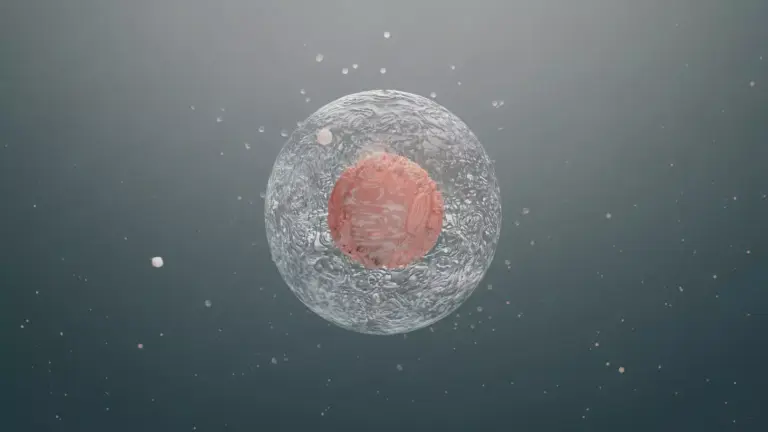

To understand radionuclide bone scanning, we explore radioactive tracers and their interaction with bone. This imaging technique gives us insights into bone health.

The Radioactive Isotope Process

A small amount of a radioactive isotope, like Technetium-99m methylene diphosphonate (Tc-99m MDP), is injected into the bloodstream. This isotope is drawn to active bone areas, like those with cancer, infection, or fractures.

The isotope builds up in the bone, emitting gamma rays. A gamma camera captures these rays, creating images of bone activity. These images help us spot abnormal bone areas.

Mechanism of Detecting Bone Abnormalities

The technique works by showing where the isotope builds up more. Cancer, for instance, can make bones more active, leading to more isotope uptake.

This increased uptake shows up on the images. It helps us find problems that might not show up on other scans.

Bone Metabolism and Tracer Uptake

Bone metabolism affects how much isotope is taken up. Areas with high bone activity, like those with cancer, take up more isotope.